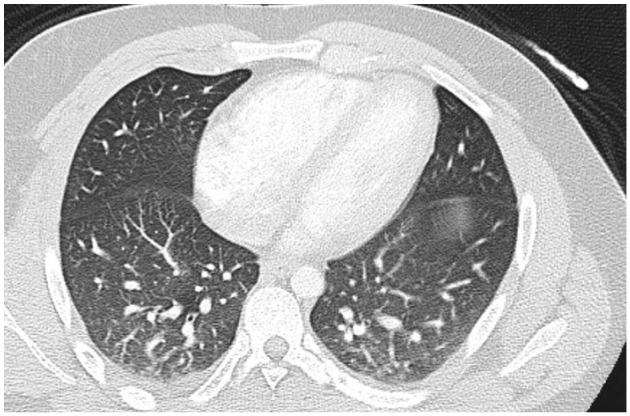

Severe acute respiratory syndrome coronavirus 2 causes coronavirus disease 2019 (COVID-19), which has become a global pandemic. Apart from the mild features of the disease, long-term complications involve many systems including both endocrine and cardiovascular systems. Myocarditis, secondary to COVID-19, has become a well-known complication of the disease. However, endocrine complications are generally not common, particularly isolated pituitary abnormalities. There is one other report of diabetes insipidus developing as a late sequela of COVID-19. In this article, we report a case of a young male who presented with features of myocarditis but developed diabetes insipidus on day 7 of admission as a long-term complication after recovery from COVID-19 infection. His laboratory test results at the time of developing the complication revealed a high serum sodium level and low urine osmolality. The patient recovered on administration of desmopressin and was discharged after 16 days of hospitalization.

严重急性呼吸综合征冠状病毒 2 引起的冠状病毒病 2019(COVID-19)已成为全球性大流行疾病。除了疾病的轻度特征外,长期并发症涉及许多系统,包括内分泌和心血管系统。继发于 COVID-19 的心肌炎已成为该疾病的一个众所周知的并发症。然而,内分泌并发症通常并不常见,特别是孤立性垂体异常。还有一份关于糖尿病性尿崩症作为 COVID-19 的晚期后遗症发展的报告。在本文中,我们报告了一例年轻男性,他因 COVID-19 感染康复后出现心肌炎的特征,但在入院第 7 天出现糖尿病性尿崩症作为长期并发症。他在发生并发症时的实验室检查结果显示血清钠水平高和尿渗透压低。患者在给予去氨加压素后康复,并在住院 16 天后出院。